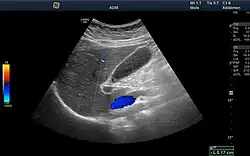

Ultrasound

Medical ultrasound uses high frequency broadband sound waves in the megahertz range that are reflected by tissue to varying degrees to produce (up to 3D) images. This is commonly associated with imaging the fetus in pregnant women. Uses of ultrasound are much broader, however. Other important uses include imaging the abdominal organs, heart, breast, muscles, tendons, arteries and veins. While it may provide less anatomical detail than techniques such as CT or MRI, it has several advantages which make it ideal in numerous situations, in particular that it studies the function of moving structures in real-time, emits no ionizing radiation, and contains speckle that can be used in elastography. Ultrasound is also used as a popular research tool for capturing raw data, that can be made available through an ultrasound research interface, for the purpose of tissue characterization and implementation of new image processing techniques. The concepts of ultrasound differ from other medical imaging modalities in the fact that it is operated by the transmission and receipt of sound waves. The high frequency sound waves are sent into the tissue and depending on the composition of the different tissues; the signal will be attenuated and returned at separate intervals. A path of reflected sound waves in a multilayered structure can be defined by an input acoustic impedance (ultrasound sound wave) and the Reflection and transmission coefficients of the relative structures.[20] It is very safe to use and does not appear to cause any adverse effects. It is also relatively inexpensive and quick to perform. Ultrasound scanners can be taken to critically ill patients in intensive care units, avoiding the danger caused while moving the patient to the radiology department. The real-time moving image obtained can be used to guide drainage and biopsy procedures. Doppler capabilities on modern scanners allow the blood flow in arteries and veins to be assessed.